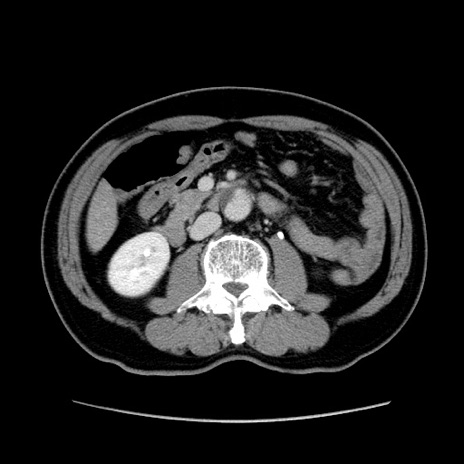

症例34(横断像)

【症例】60歳代 男性

【主訴】右鼠径部膨隆

【現病歴】1年程前より右鼠径部膨隆あり。自己にて還納可能だったため放置していた。3時間前より右鼠径部の脱出を認め、還納困難となり受診。

【既往歴】高血圧

【身体所見】右鼠径部に小児頭大の膨隆あり。弾性硬であり、用手還納は困難。左鼠径部にも膨隆を認める。脱出はなし。

【データ】WBC 15500、CRP 測定なし